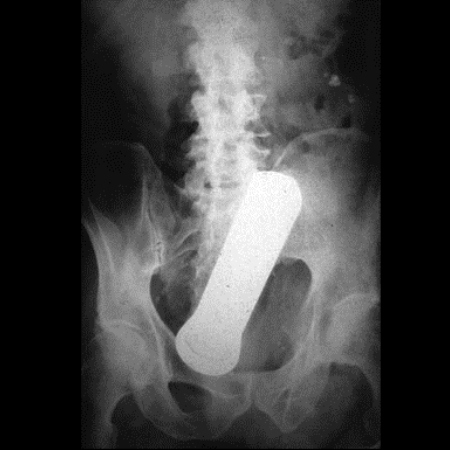

"สากกะเบือในทวารหนักชายวัย 40 ปี เขาอ้างว่าสากหลุดเข้าไปแบบนี้ได้ เพราะเป็นอุบัติเหตุระหว่างทำอาหาร"